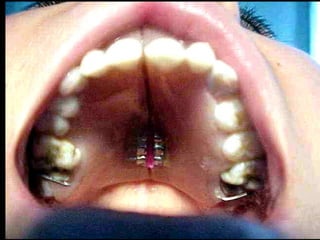

Pulpitis Crónica Hiperplásica

Imagen clínica. Observe en la diapositiva un primer molar inferior

de un niño de 12 años cuya cara oclusal tiene una cavidad de caries;

toda ella ocupada por una gran masa carnosa rosada correspondiente

a un pólipo pulpar que protruye de la pulpa.

Pulpitis Crónica Hiperplásica.

Vemostejido dentario correspondiente ala corona de un molar destruido por la

cariesy protuyendo de la cámara pulparuna lesión en forma de “hongo” el cual

es el pólipo pulpar.

Mayor aumento. Observe en la diapositiva la misma lesión fungiforme en una

vista más cercana donde vemos que está tapizado por epitelio plano estratificado

igual y proveniente de la mucosa bucal. Debajo del epitelio vemos el corion de

tejido conjuntivo y un infiltrado inflamatorio crónico.